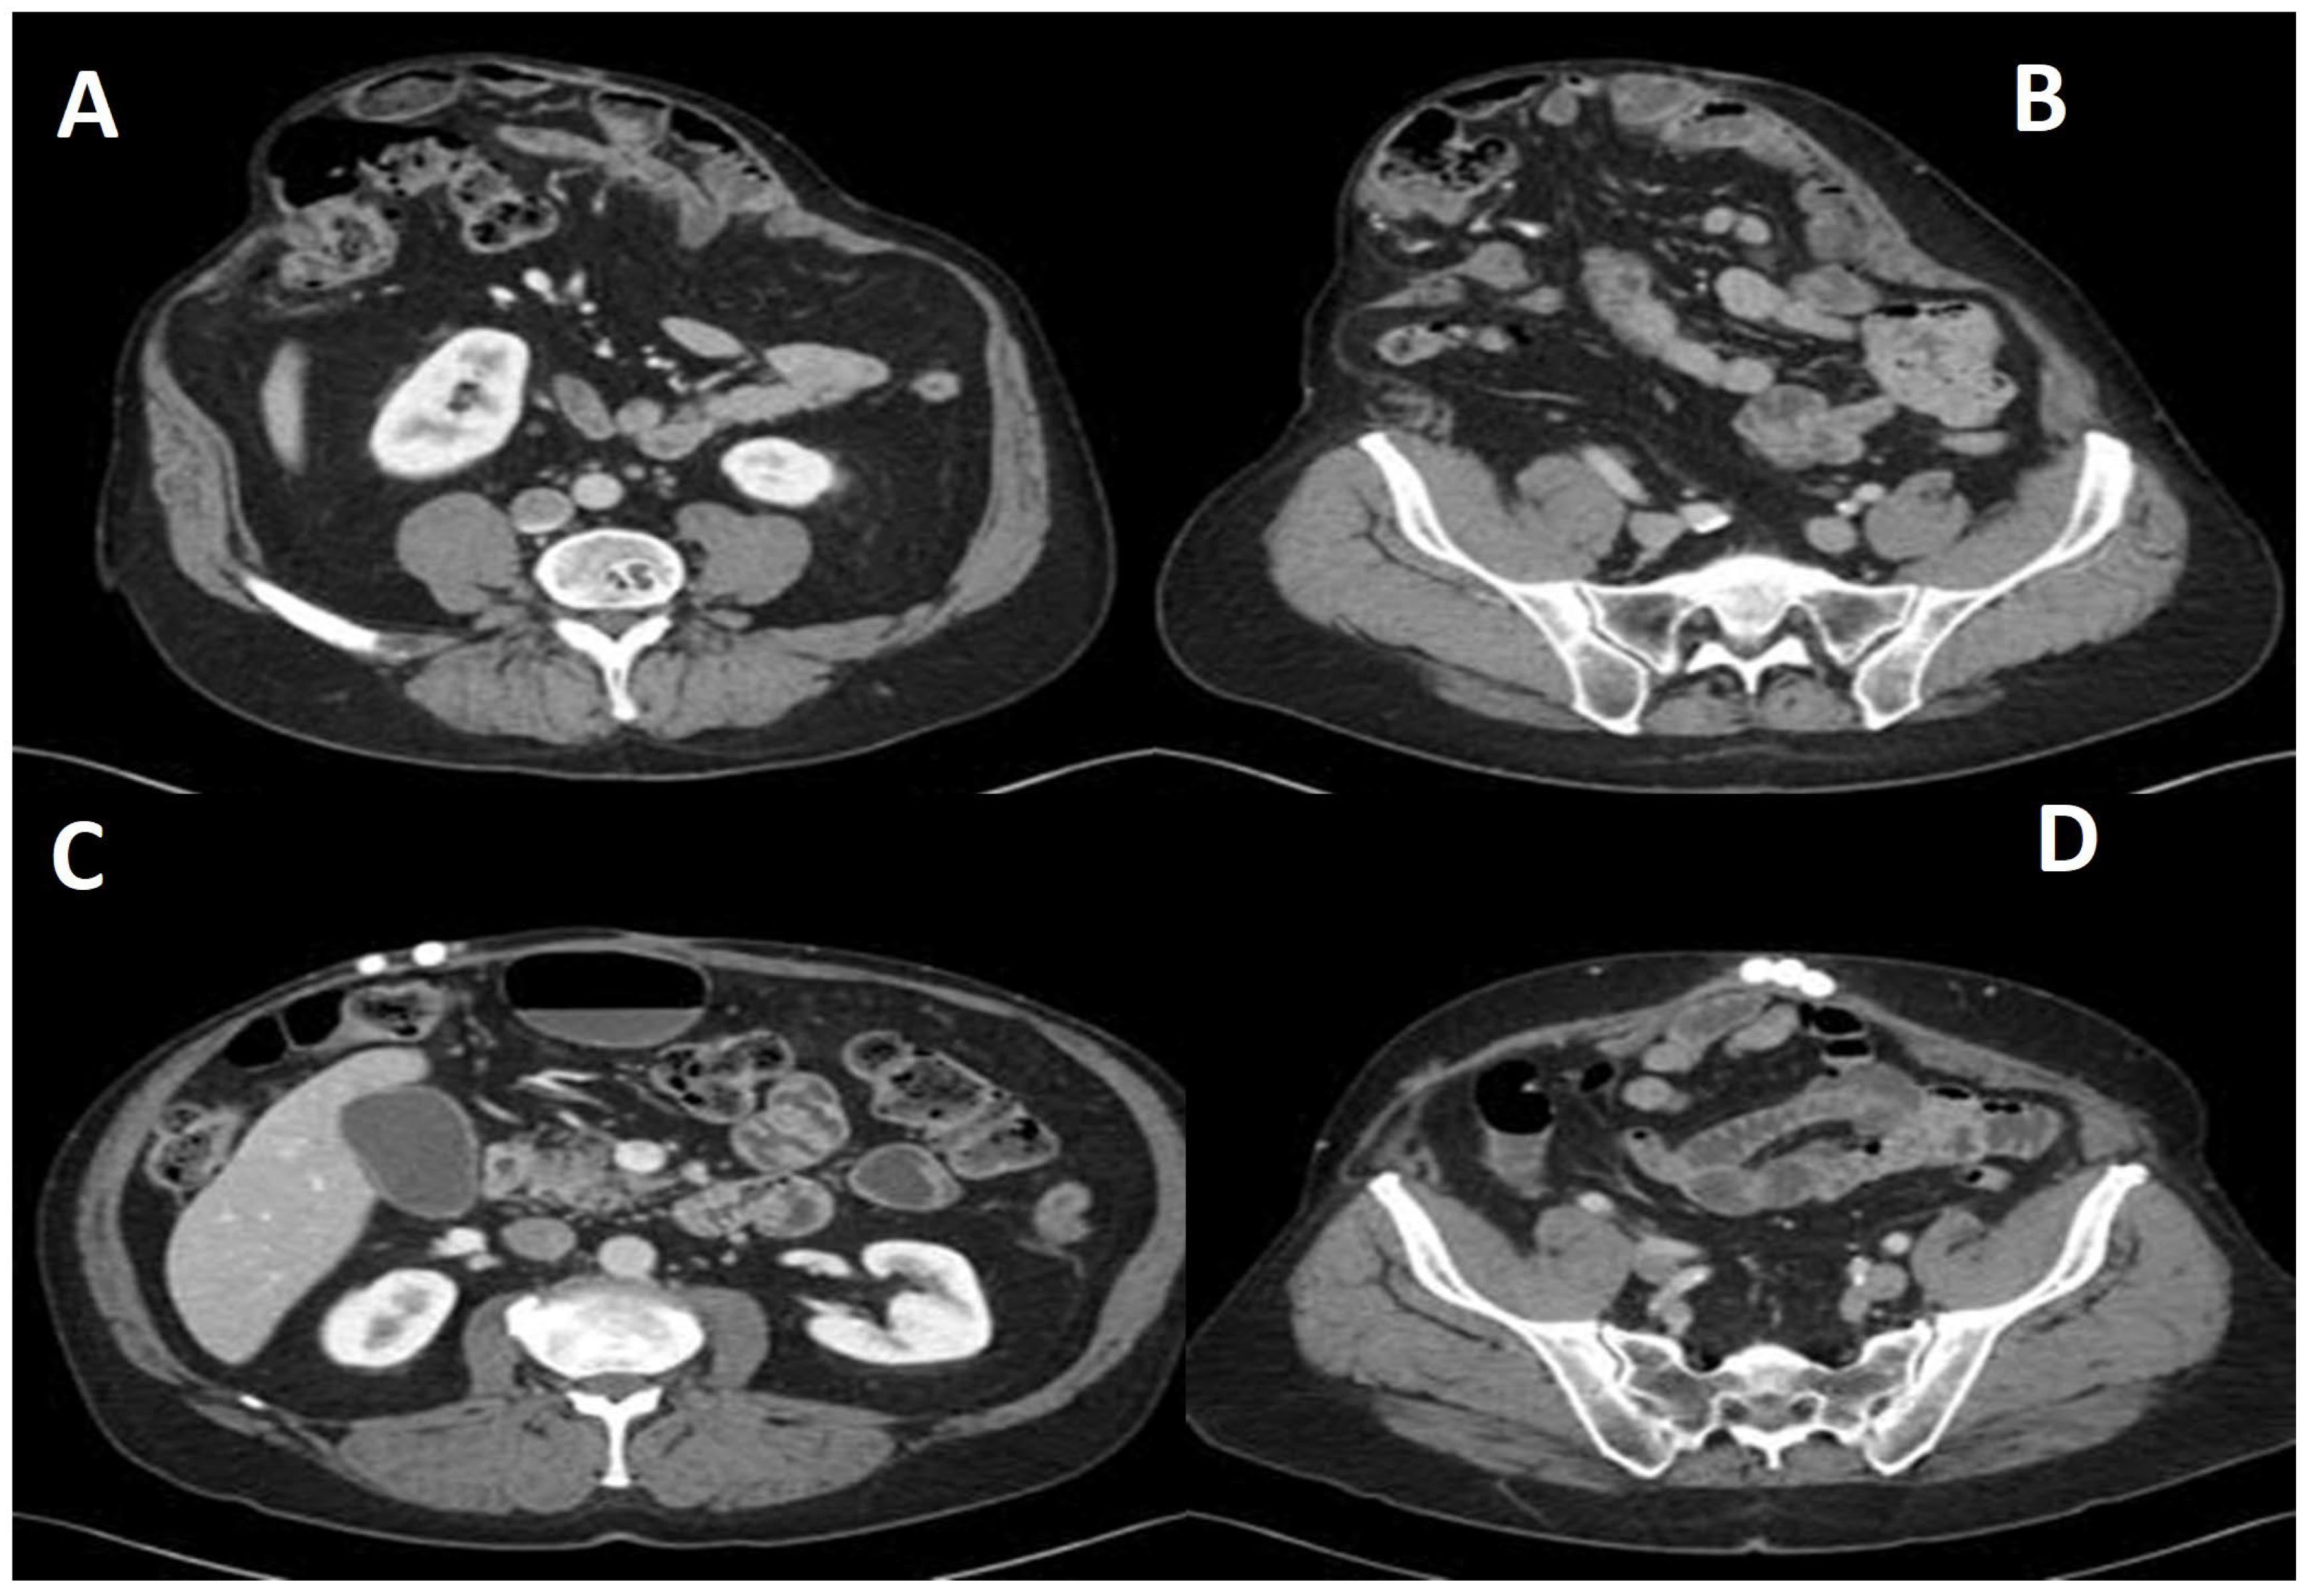

Patients were evaluated by one of four surgeons offering this palliative approach. Initial assessments included the history, physical examination, and contrast-enhanced abdominal/pelvic CT imaging (Figure 1A,B). Hernioplasty was reserved for patients without expected need for future laparotomy. For those without prior cholecystectomy, ultrasound was performed to assess cholelithiasis; if present, cholecystectomy was offered as a staged procedure during the same admission. Patients with infected mesh underwent staged total mesh explantation, with particular care taken to preserve anatomical integrity.

Preoperative details for the 43 identified patients are presented in Table 1. Urgent repair, defined as surgery during the same hospital admission following acute presentation, was performed in 14 patients (32.5%). Overall, non-absorbable polypropylene mesh was implanted in 26 patients, while bioprosthetic or absorbable mesh was used in the remaining 17 cases. The mean surface area of implanted mesh was 561 cm2. Antibiotic bead exchange was performed in 38 patients (88.3%), and the beads remained indwelling (Figure 1 C&D) in 28 patients (65.1%) at the time of last follow-up (Table 2).

Figure 1. (A,B) Axial section of the preoperative CT scan shows a large ventral hernia with loss of domain. (C,D) Axial section of the postoperative CT scan shows hernia repair with antibiotic beads in situ.